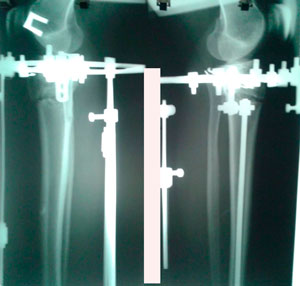

РЕНТГЕН ДО ОПЕРАЦИИ